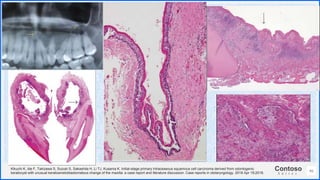

Kikuchi K, Ide F, Takizawa S, Suzuki S, Sakashita H, Li TJ, Kusama K. Initial-stage primary intraosseous squamous cell carcinoma derived from odontogenic

keratocyst with unusual keratoameloblastomatous change of the maxilla: a case report and literature discussion. Case reports in otolaryngology. 2018 Apr 19;2018.

Primary intraosseous squamous

cell carcinoma (PIOSCC)

derived from an odontogenic

keratocyst (OKC) is a rare

malignant neoplasm of the jaws,

which is locally aggressive with

quite poor prognosis.